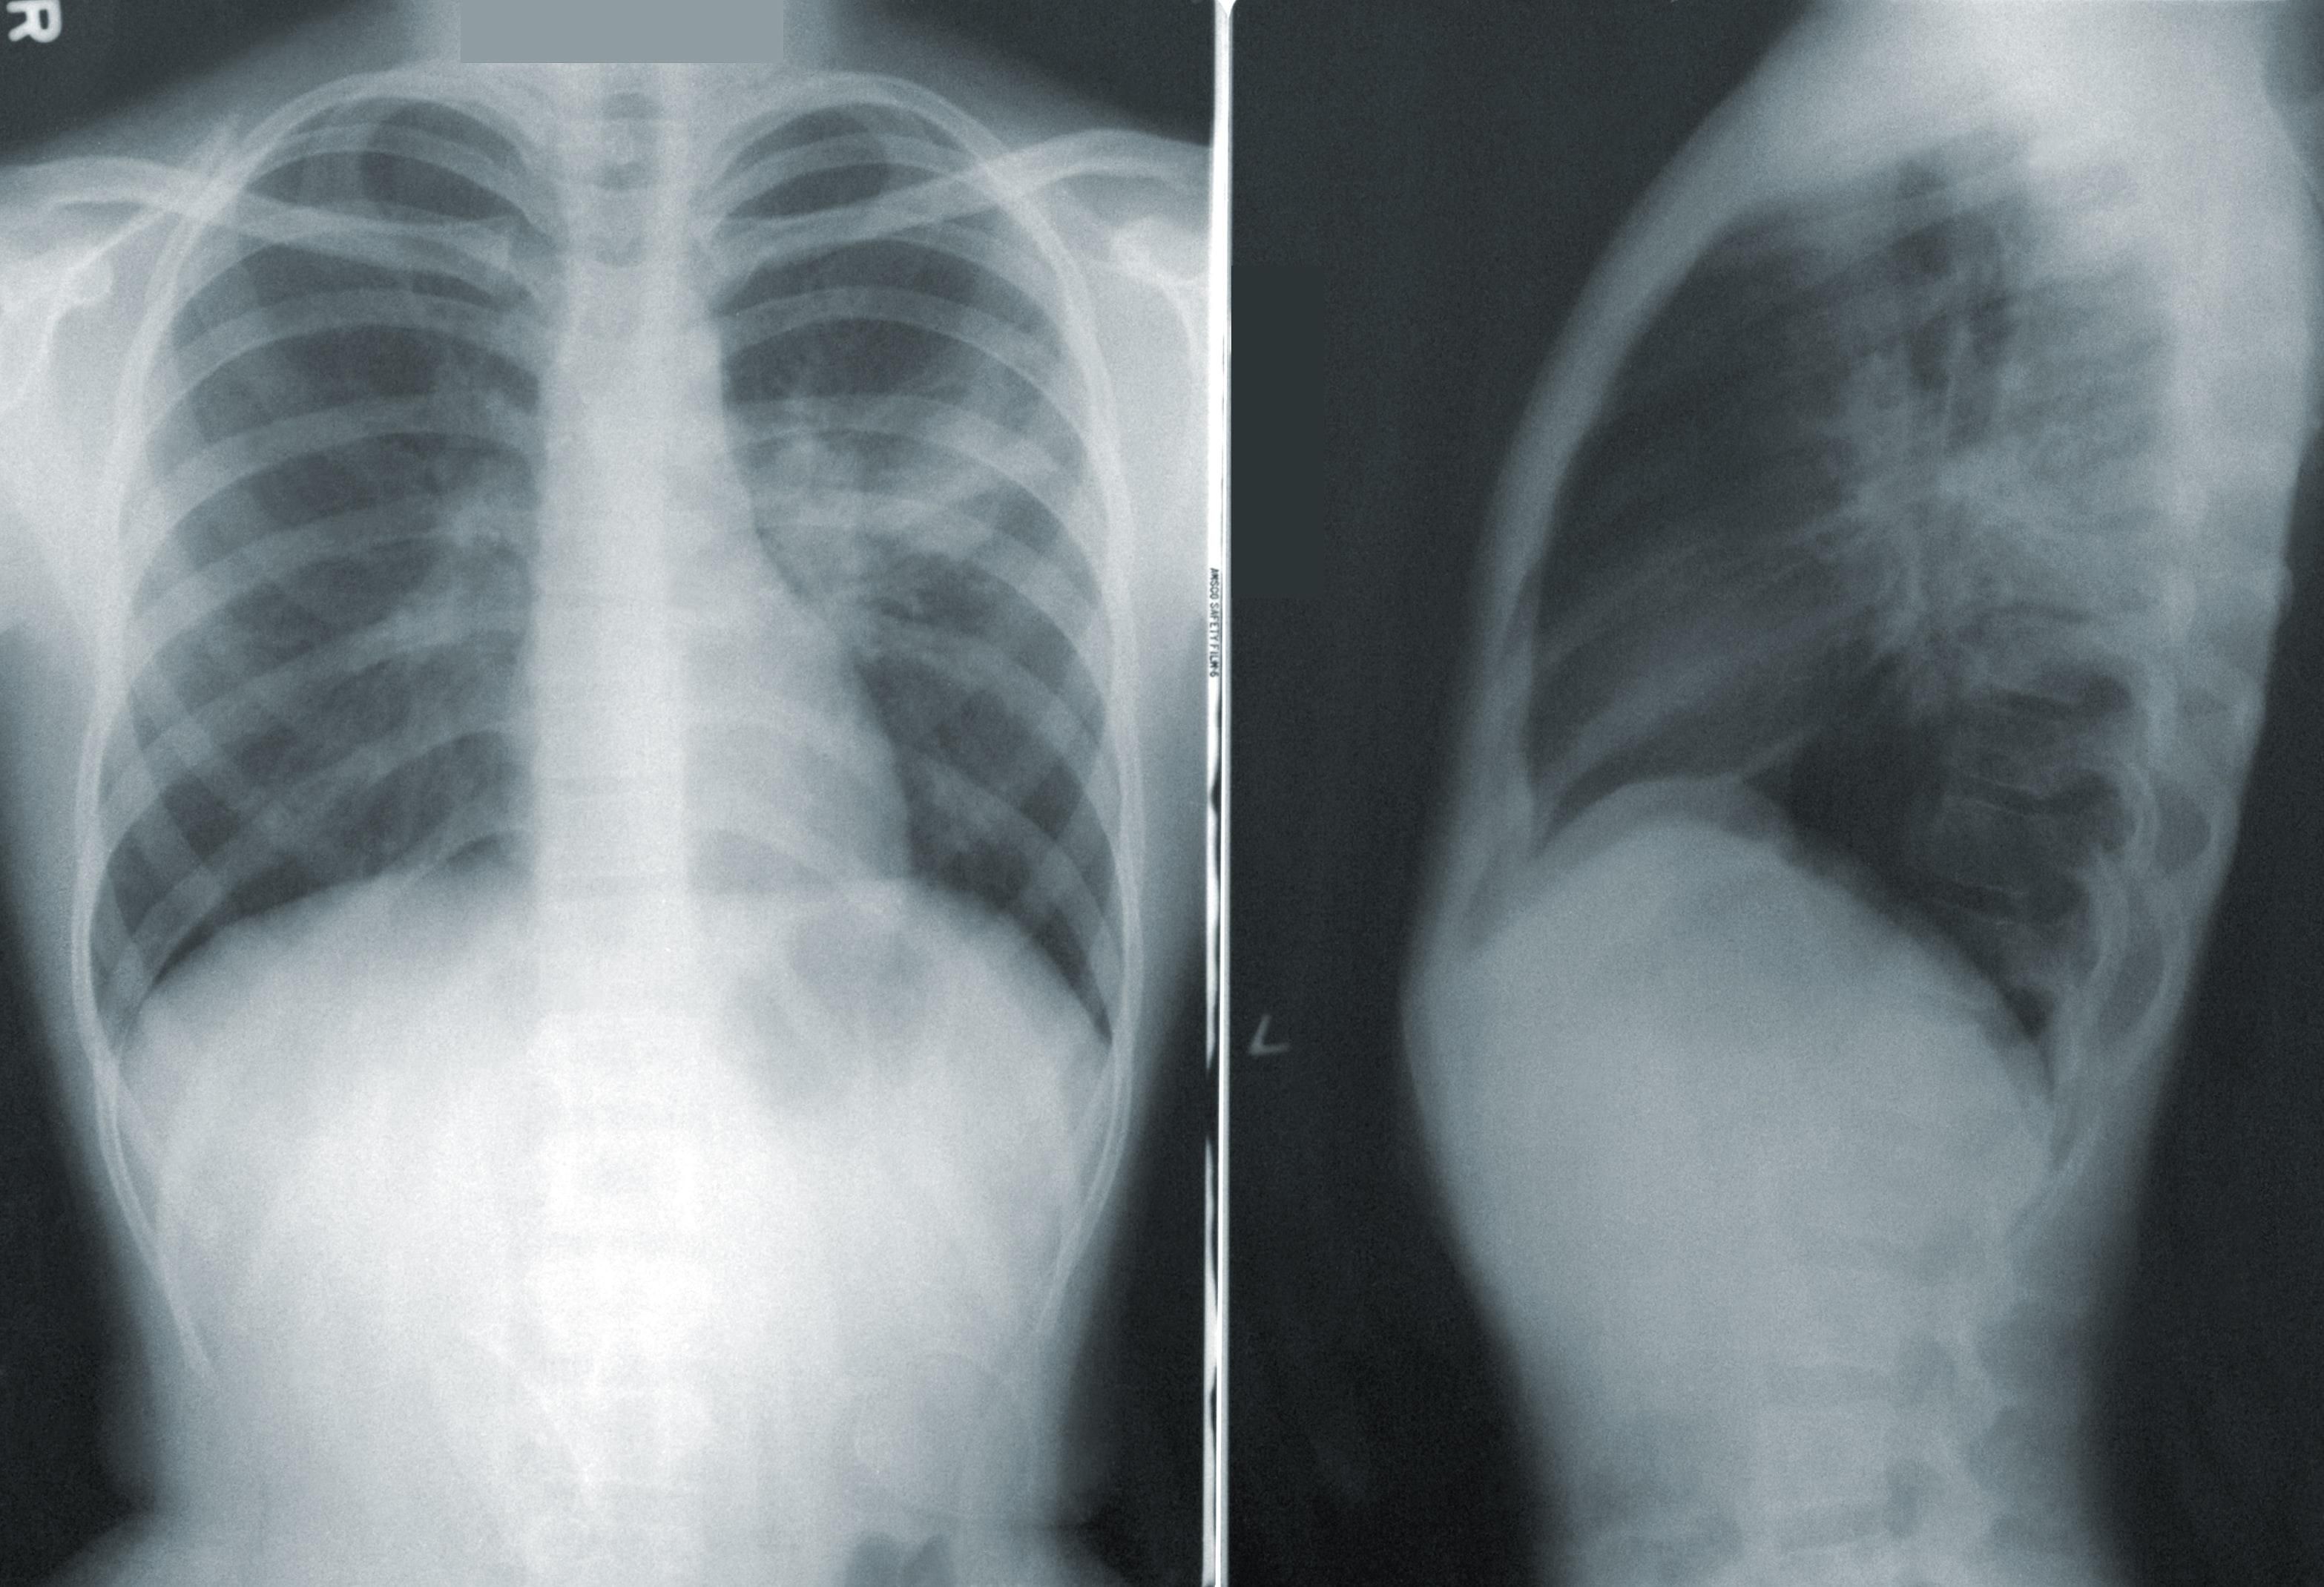

Инициативу решили начать, потому что рак легких – самая частая причина смерти среди всех онкологических заболеваний в Чехии. Как известно, курение является распространенной привычкой среди жителей страны. К тому же у большинства пациентов диагноз обнаруживают поздно: пациенты часто обращаются к медикам на стадии, когда опухоль уже не может быть прооперирована.

Врачи свяжутся с нынешними или бывшими курильщиками в возрасте от 55 до 74 лет, которые используют примерно одну пачку сигарет в день в течение 20 лет. Если пациент согласится принять участие в программе, то врач направит его на обследование в клинику. После этого будет проведен скрининг с использованием компьютерной томографии (КТ).

По словам специалистов, обследование несложное и позволяет выявить опухоль всего за несколько минут даже на ранней стадии.